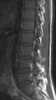

Ascending cholangitis, also known as acute cholangitis or simply cholangitis, is inflammation of the bile duct (cholangitis), usually caused by bacteria ascending from its junction with the duodenum (first part of the small intestine). It tends to occur if the bile duct is already partially obstructed by gallstones.Cholangitis can be life-threatening, and is regarded as a medical emergency. [Source: Wikipedia ]